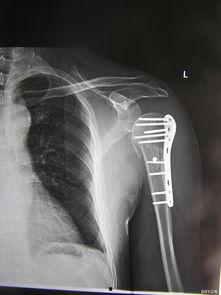

1. 手术过程视频:这类视频详细展示了手术的整个过程,包括麻醉、手术器械、手术步骤等。通过这些视频,你可以直观地了解手术的全貌。

2. 术前术后对比视频:这类视频展示了患者手术前后的变化,让你对手术效果有一个直观的认识。